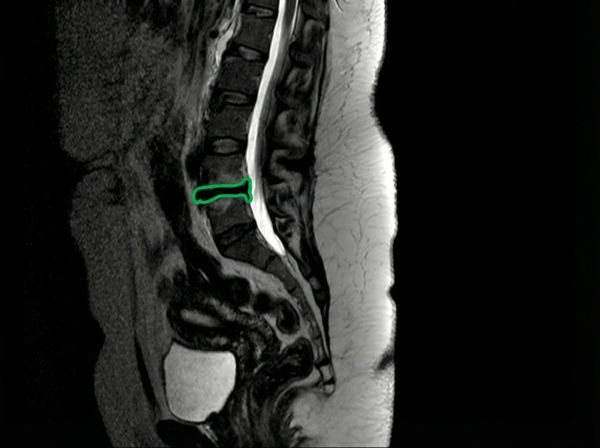

Пациентка, 45 лет. Грыжа секвестрированная, 3.5 сантиметра.

Грыжи нет, остался только рубец.